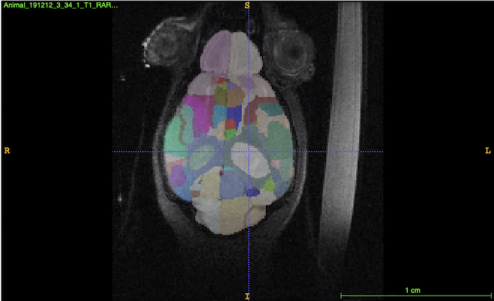

Imaging Biomarkers for Alzheimer’s Disease Using Magnetic Resonance Microscopy

BIAC co-authors Alex Badea (lead) and Jacques Stout have a book chapter "Imaging Biomarkers for Alzheimer’s Disease Using Magnetic Resonance Microscopy" published in a new edited volume Magnetic Resonance Microscopy: Instrumentation and Applications in Engineering, Life Science, and Energy Research from Wiley.